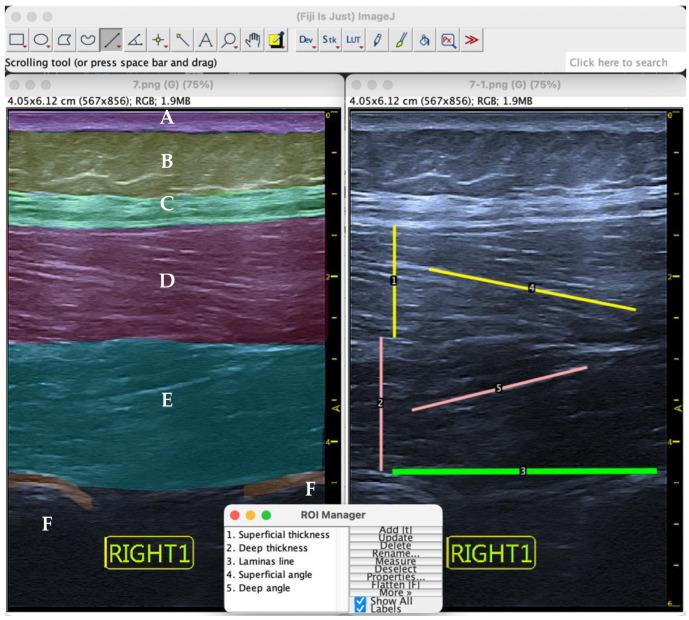

Different ultrasound images of the lumbar multifidus musculature were captured. Subsequently, with the help of ImageJ software, the pennation angle of this musculature was measured. Finally, a complex statistical analysis determined the intra- and interrater reliability.

方法

采集腰多裂肌不同的超声图像。随后,借助ImageJ软件测量该肌肉组织的羽状角。最后,通过复杂的统计分析确定评分者内和评分者间的可靠性。